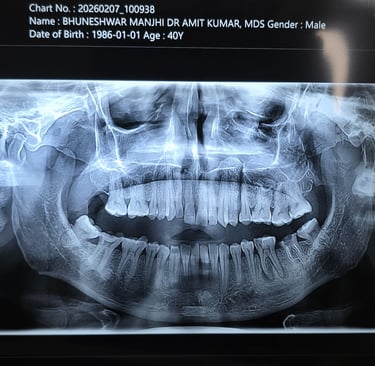

Diagnosis Done:

Clinical check-up

X-ray / OPG

CT Scan (if needed)